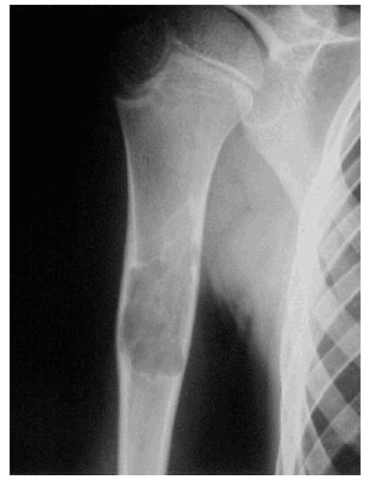

• Me operan en el brazo por un quiste oseo

Me operan en el brazo por un quiste oseo